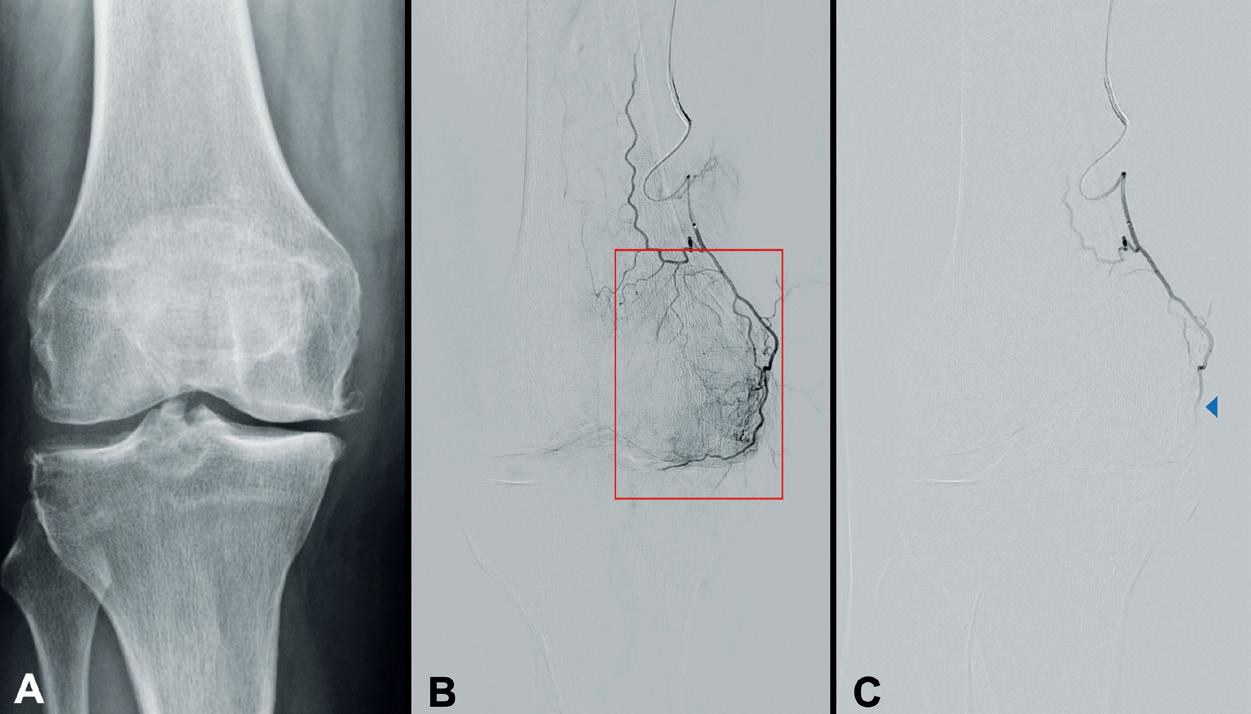

Drug-coated balloons (DCBs) and stents were not associated with reduced risk of amputation or improved quality of life compared with uncoated devices in the SWEDEPAD 1 and 2 trials. In addition, higher five-year mortality with drug-coated devices in patients with intermittent claudication was noted, leading researchers to stress that the safety of paclitaxel-coated devices is an “ongoing discussion”.

SWEDEPAD 1 AND 2 WERE pragmatic, participant-blinded, registrybased randomised trials that set out to determine the clinical impact of drug-coated technology on patients with peripheral arterial disease (PAD). Late-breaking findings from the trial were presented at the 2025 European Society of Cardiology (ESC) congress (29 August–1 September, Madrid, Spain) and simultaneously published in The Lancet.

Explaining the rationale for the trials at ESC, co-principal investigator Joakim Nordanstig (University of Gothenburg, Gothenburg, Sweden), said: “Drugcoated balloons and stents have been shown to reduce restenosis and the need for reinterventions in the endovascular treatment of PAD. However, there are uncertainties regarding whether drug-coated devices improve outcomes that are meaningful to patients, quality of life and reducing amputations, and there are some concerns over safety. We investigated these and other endpoints in two trials in PAD—one in chronic limbthreatening ischaemia [CLTI] and one in intermittent claudication—comparing drug-coated and uncoated devices.”

In SWEDEPAD 1, 2,355 patients with CLTI (Rutherford stage 4–6) undergoing infrainguinal endovascular treatment were randomised 1:1 to drug-coated or uncoated balloons or stents. In nearly all of the drug-coated devices implanted, the drug delivered was paclitaxel (>99%). There was no significant difference in the primary endpoint of time to ipsilateral aboveankle amputation with drug-coated versus uncoated devices (hazard ratio [HR] 1.05; 95% confidence interval [CI] 0.87–1.27) over five years of followup. Target vessel reinterventions were reduced in the drug-coated group during the first year (HR 0.81; 95% CI 0.66–0.98), but this difference disappeared with longer follow-up. There was no difference in all-cause mortality or in quality of life (as assessed using the VascuQoL-6 questionnaire).

In SWEDEPAD 2, 1,155 patients with intermittent claudication (Rutherford stage 1–3) undergoing infrainguinal endovascular treatment were randomised

1:1 after successful guidewire crossing to receive either drug-coated or uncoated balloons or stents. All drug-coated devices implanted delivered paclitaxel. There was no difference in the primary efficacy endpoint of quality of life between the drug-coated and uncoated groups at 12 months (mean difference in VascuQoL-6 scores: –0.02; 95% CI –0.66–0.62). Target vessel reintervention rates were not different at one year or over a median follow-up of 6.2 years. All-cause mortality did not differ over 7.1 years (HR 1.18; 95% CI 0.94–1.48), although higher five-year mortality was noted with drug-coated versus uncoated devices (HR 1.47; 95% CI 1.09–1.98).

Summarising the findings, coprincipal investigator Mårten Falkenberg (Sahlgrenska University Hospital and the University of Gothenburg, Gothenburg, Sweden), said: “Paclitaxel-coated devices were not effective in preventing amputation in chronic limb-threatening ischaemia or improving quality of life in intermittent claudication. Given the signal of increased mortality with intermittent claudication, clinicians should carefully evaluate the potential risks and benefits when considering these expensive devices. Devices incorporating antiproliferative agents other than paclitaxel warrant further investigation in PAD.”